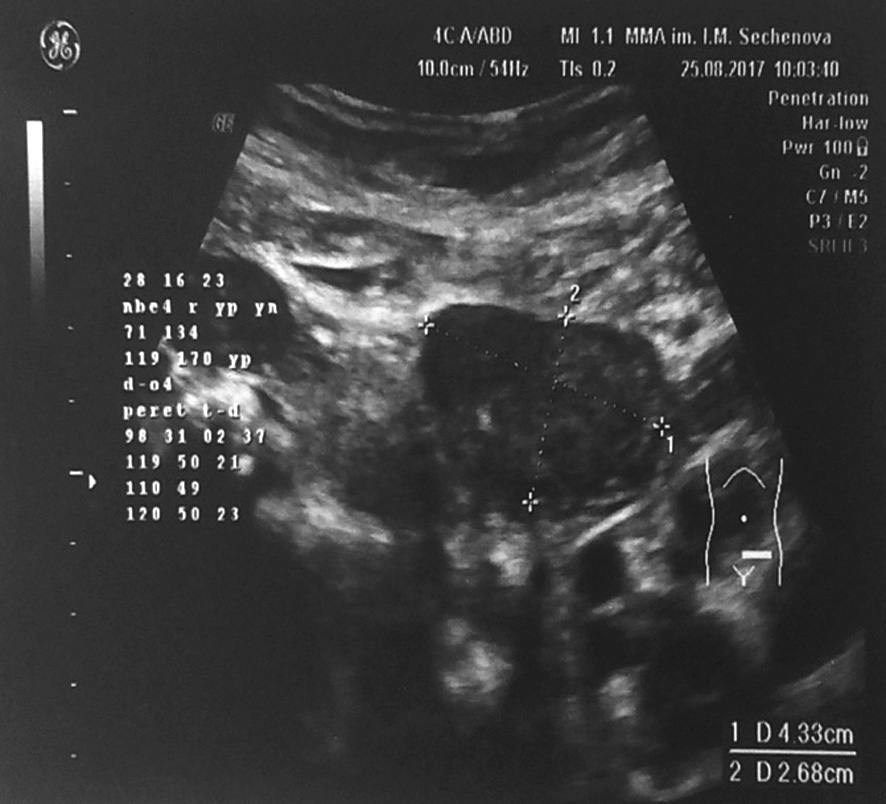

3. Fig. 3. Ultrasound of the pelvic organs. The increase in size and structural changes in the left ovary (43 × 27 × 42 mm). Enlarged uterus (61 × 52 × 75 mm), uterine fibroids of different sizes. | |